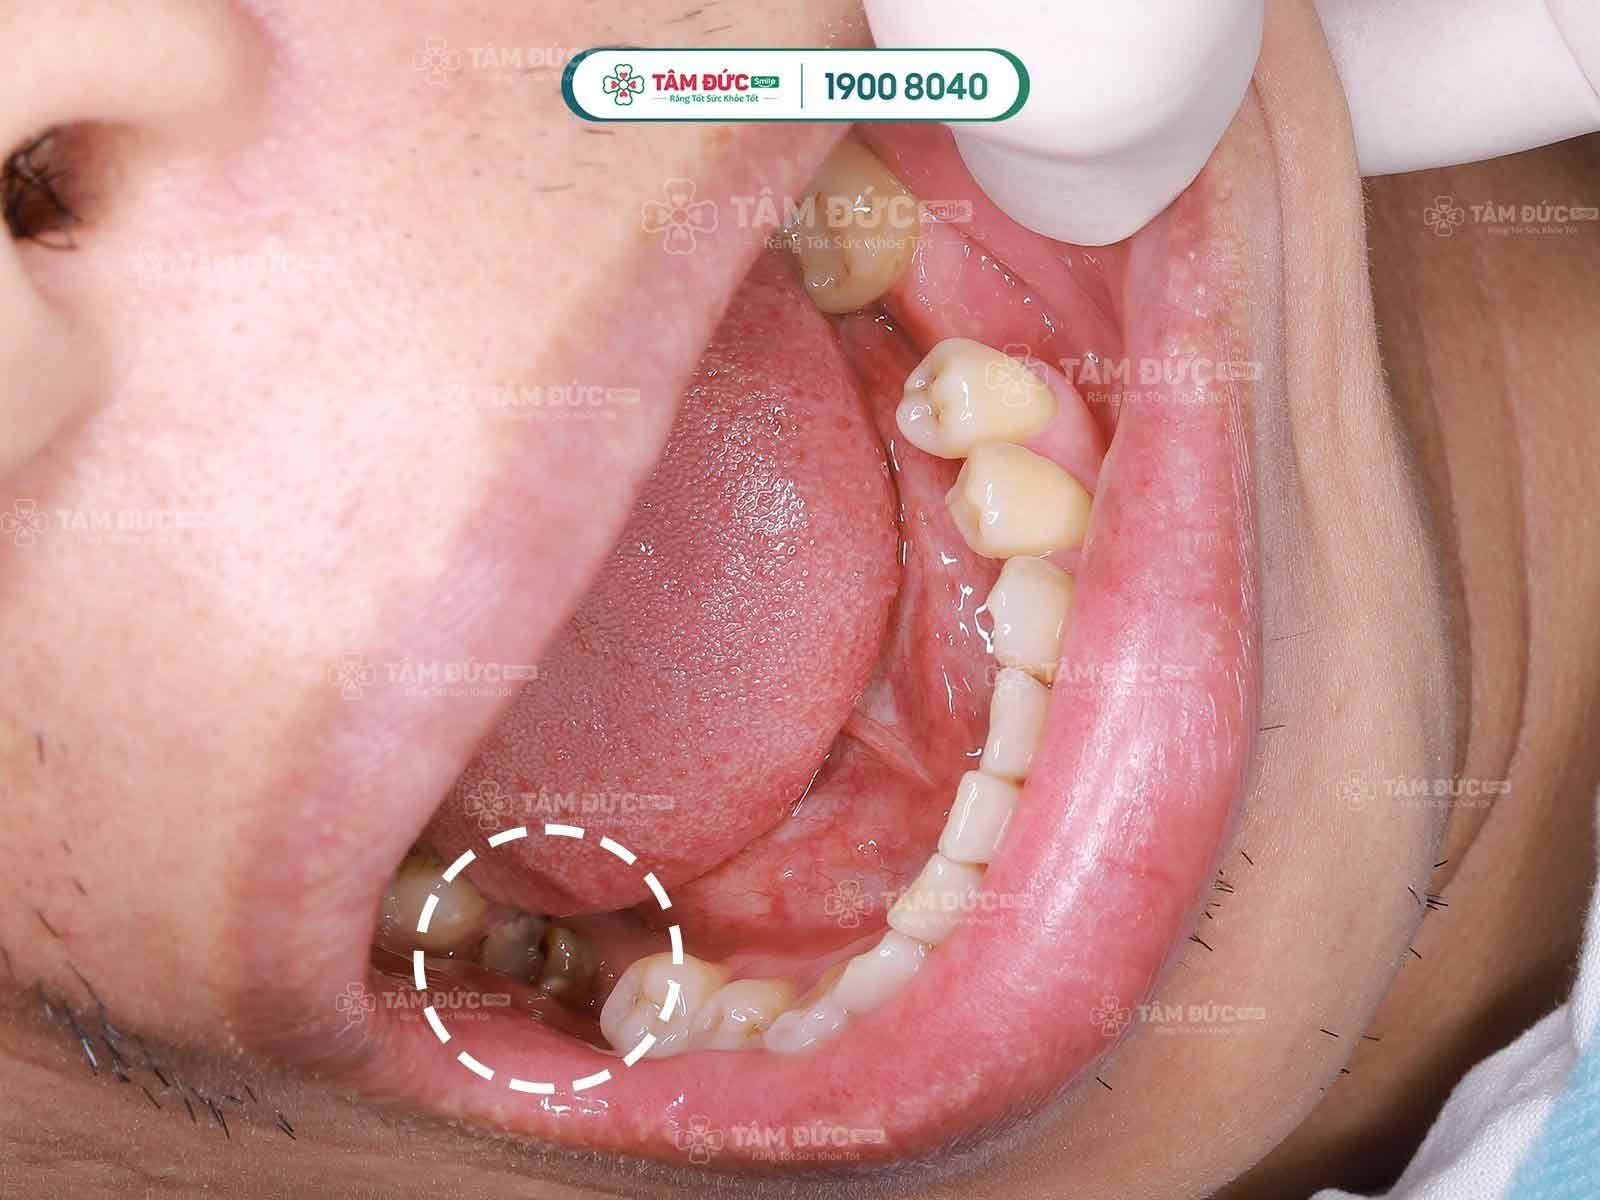

Thường nguyên nhân chính dẫn đến viêm tủy là sâu răng, các mảng bám từ thức ăn lâu ngày không được vệ sinh sẽ hình thành vôi răng, trong vôi răng đó chứa rất nhiều vi khuẩn có khả năng phá hủy, ăn mòn răng của Quý khách xuất hiện tình trạng răng xuất hiện các lỗ đen. Và kéo dài tình trạng này lâu, vi khuẩn sẽ ăn mòn lớp răng vào đến tủy, gây viêm tủy.

Các bệnh nhân sâu ăn vào đến tủy thường sẽ cảm thấy đau nhức răng, ăn nhai khó khăn, ảnh hưởng xấu đến sức khỏe.

- Răng bị mẻ, vỡ lớn, sâu răng làm lộ tủy gây viêm tủy, nhiễm trùng.